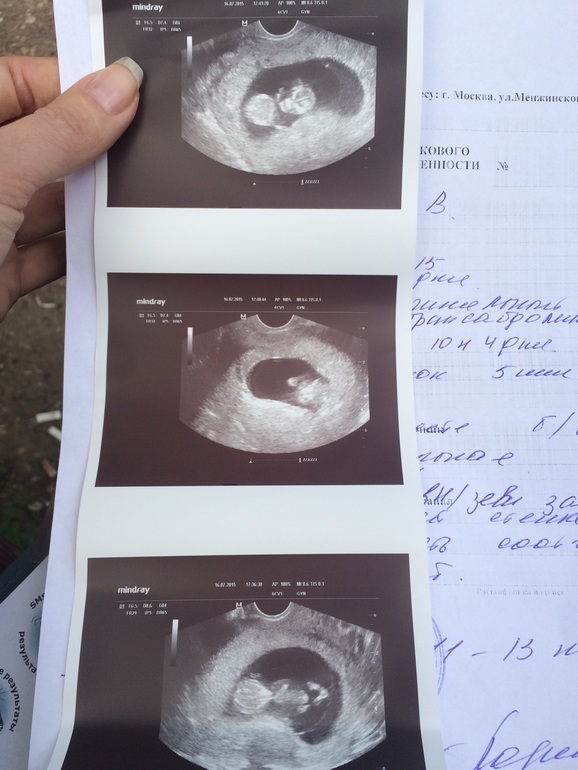

УЗИ, КТГ, доплерПод впечатлением)) жаль мужа не позвала, я не думала, что уже все видно, ручки, ножки, пальчики. А сердечко-то как бьется. 99%девочка. По срокам опережаем на неделю от пдм. Теперь ждем 1-й скрининг и дальше наслаждаться беременностью( если б не токс, черт его за ногу).

Да самое главное мы растем)) а так мне по УЗИ срок поставили 10 нед. 5 дней. Сколько врачей-столько мнений, я вчера видео насмотрелась, так что все возможно и на ранних сроках разглядеть.